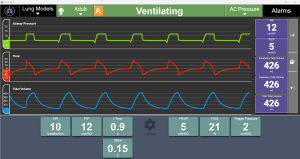

... Productos > Software de ventilación virtual RespiSim Software de ventilación virtual RespiSim Transforme la forma de impartir formación en ventilación mecánica, desde cualquier lugar y a cualquier persona Aproveche la ...

IngMar Medical